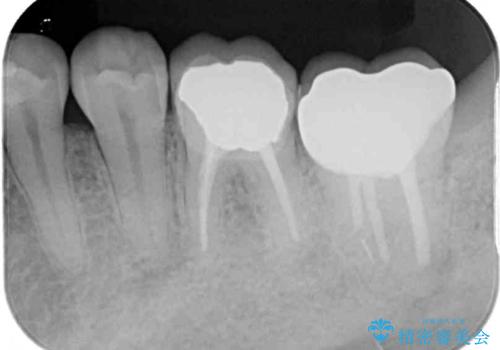

下顎の1番奥の歯であり、歯肉に覆われている部分が大きいためセラミックの十分な厚みが取れない状態でした。

強化セラミックを用いたオールセラミッククラウンにて補綴治療を行うこととしました。

十分な土台の高さを確保できない状態であったので、維持力のある土台の形態に整えることで、極力長持ちする治療を心がけました。